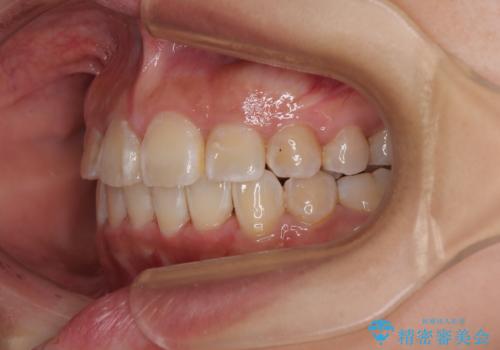

- 上下前歯のデコボコを気にして来院された患者様です。

上顎は両側の犬歯が骨内に埋伏しており、乳歯が残存している状態でした。

歯肉内に埋もれている場合には牽引することも可能ですが、両歯ともに骨内に完全に埋もれていたため、牽引することは不可能と判断しました。

口元の突出感があるわけではなく、叢生の程度もシビアではありませんでしたが、顎骨が小さく、左右ともに最後臼歯が歯肉に埋もれているため、下顎は左右第二小臼歯を抜歯することとしました。

上顎は左右ともに残存している乳歯を抜歯し、上下歯列を整えることとしました。